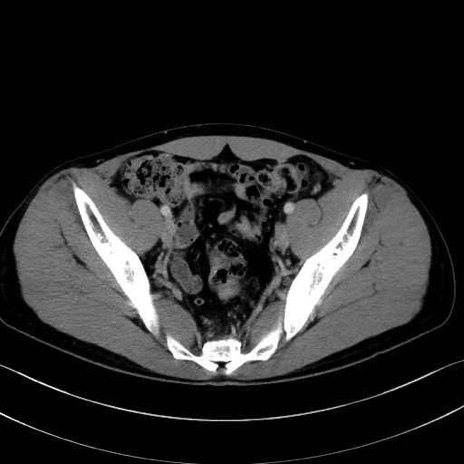

大腰筋 (Psoas major)

腸骨筋 (Iliacus)